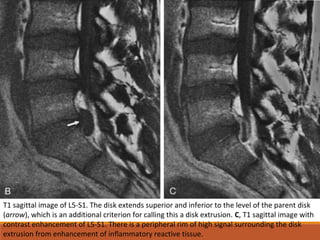

T1 sagittal image of L5-S1. The disk extends superior and inferior to the level of the parent disk

(arrow), which is an additional criterion for calling this a disk extrusion. C, T1 sagittal image with

contrast enhancement of L5-S1. There is a peripheral rim of high signal surrounding the disk

extrusion from enhancement of inflammatory reactive tissue.